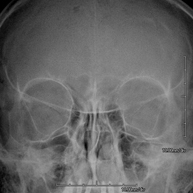

- RX Crani

Tècnica que usa els raigs X a través de la qual s'obtenen imatges del crani per al seu estudi. Indicacions: traumatisme, tancament precoç de sutures cranials. - RX Sins Paranasals

Tècnica que usa els raigs X a través de la qual s'obtenen imatges dels sins paranasals per al seu estudi. Indicacions: dificultat respiratòria nasal, tos crònica, cefalea, mucositat - RX ATM (Articulació Temporo-Mandibular)

Tècnica que usa els raigs X a través de la qual s'obtenen imatges de les òrbites per al seu estudi. Indicacions: cos estrany ocular, traumatisme, infeccions. - RX Mandibular